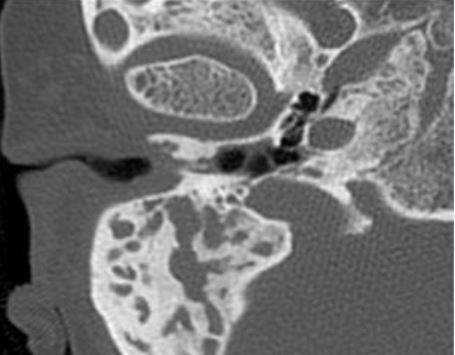

Снимок (томограмма) височных костей в осевой проекции

Во время КТ получают послойные снимки височной кости и окружающих тканей в трех плоскостях. Толщина среза составляет всего несколько миллиметров, что позволяет врачу-рентгенологу рассмотреть не только все анатомические образования, но и минимальные патологические изменения.

На полученных снимках хорошо видны следующие структуры: